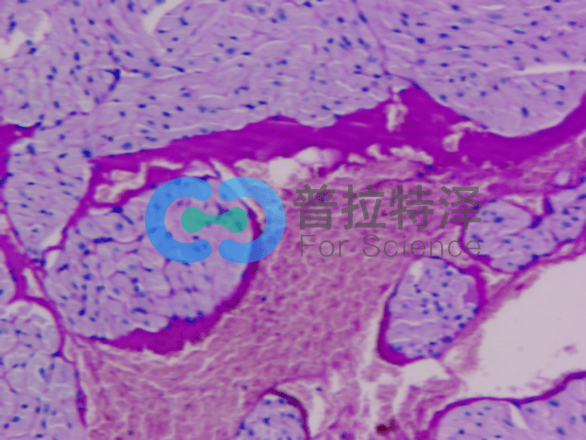

在生物學和醫學領域,PAS染色(Periodic Acid-Schiff Stain)是一種常用的組織染色技術,用于檢測組織中的多糖類物質,如糖原和粘多糖。掌握PAS染色的正確步驟,對于科研人員和醫學工作者來說至關重要。普拉特澤生物——組織染色實驗平臺操作各類組織的染色實驗上百例,專業代做PAS染色和各種染色實驗,本文將從入門到精通,全面介紹PAS染色的步驟和注意事項。

→蘇木精復染:用蘇木精對切片進行復染,使細胞核呈現藍色。